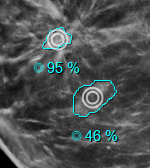

Support ScreenPoint Transpara CAD

The viewer supports ScreenPoint’s Transpara CAD objects.

The CAD header with the Transpara logo contains the number of calcification and mass findinds, the algorithm version and the Transpara score (integer value between 0 and 10).

Calcifications are marked by a diamond outline and the contour of individual calcifications.

Masses are marked by their contour (plus the default marker if enabled).

There’s an additional type of finding for Screenpoint called “decision support”, which describes a more general region of interest. So far, Transpara is the only CAD that uses this type but this might change in the future. In order to have a more general tool, the viewer refers to this type of finding as “region of interest”.

A new option has been added to both the global and local CAD menu to show/hide regions of interest. The default is off.

In case of Transpara, regions of interest appear as color-coded circles that usually - but not always - have a score associated with them.